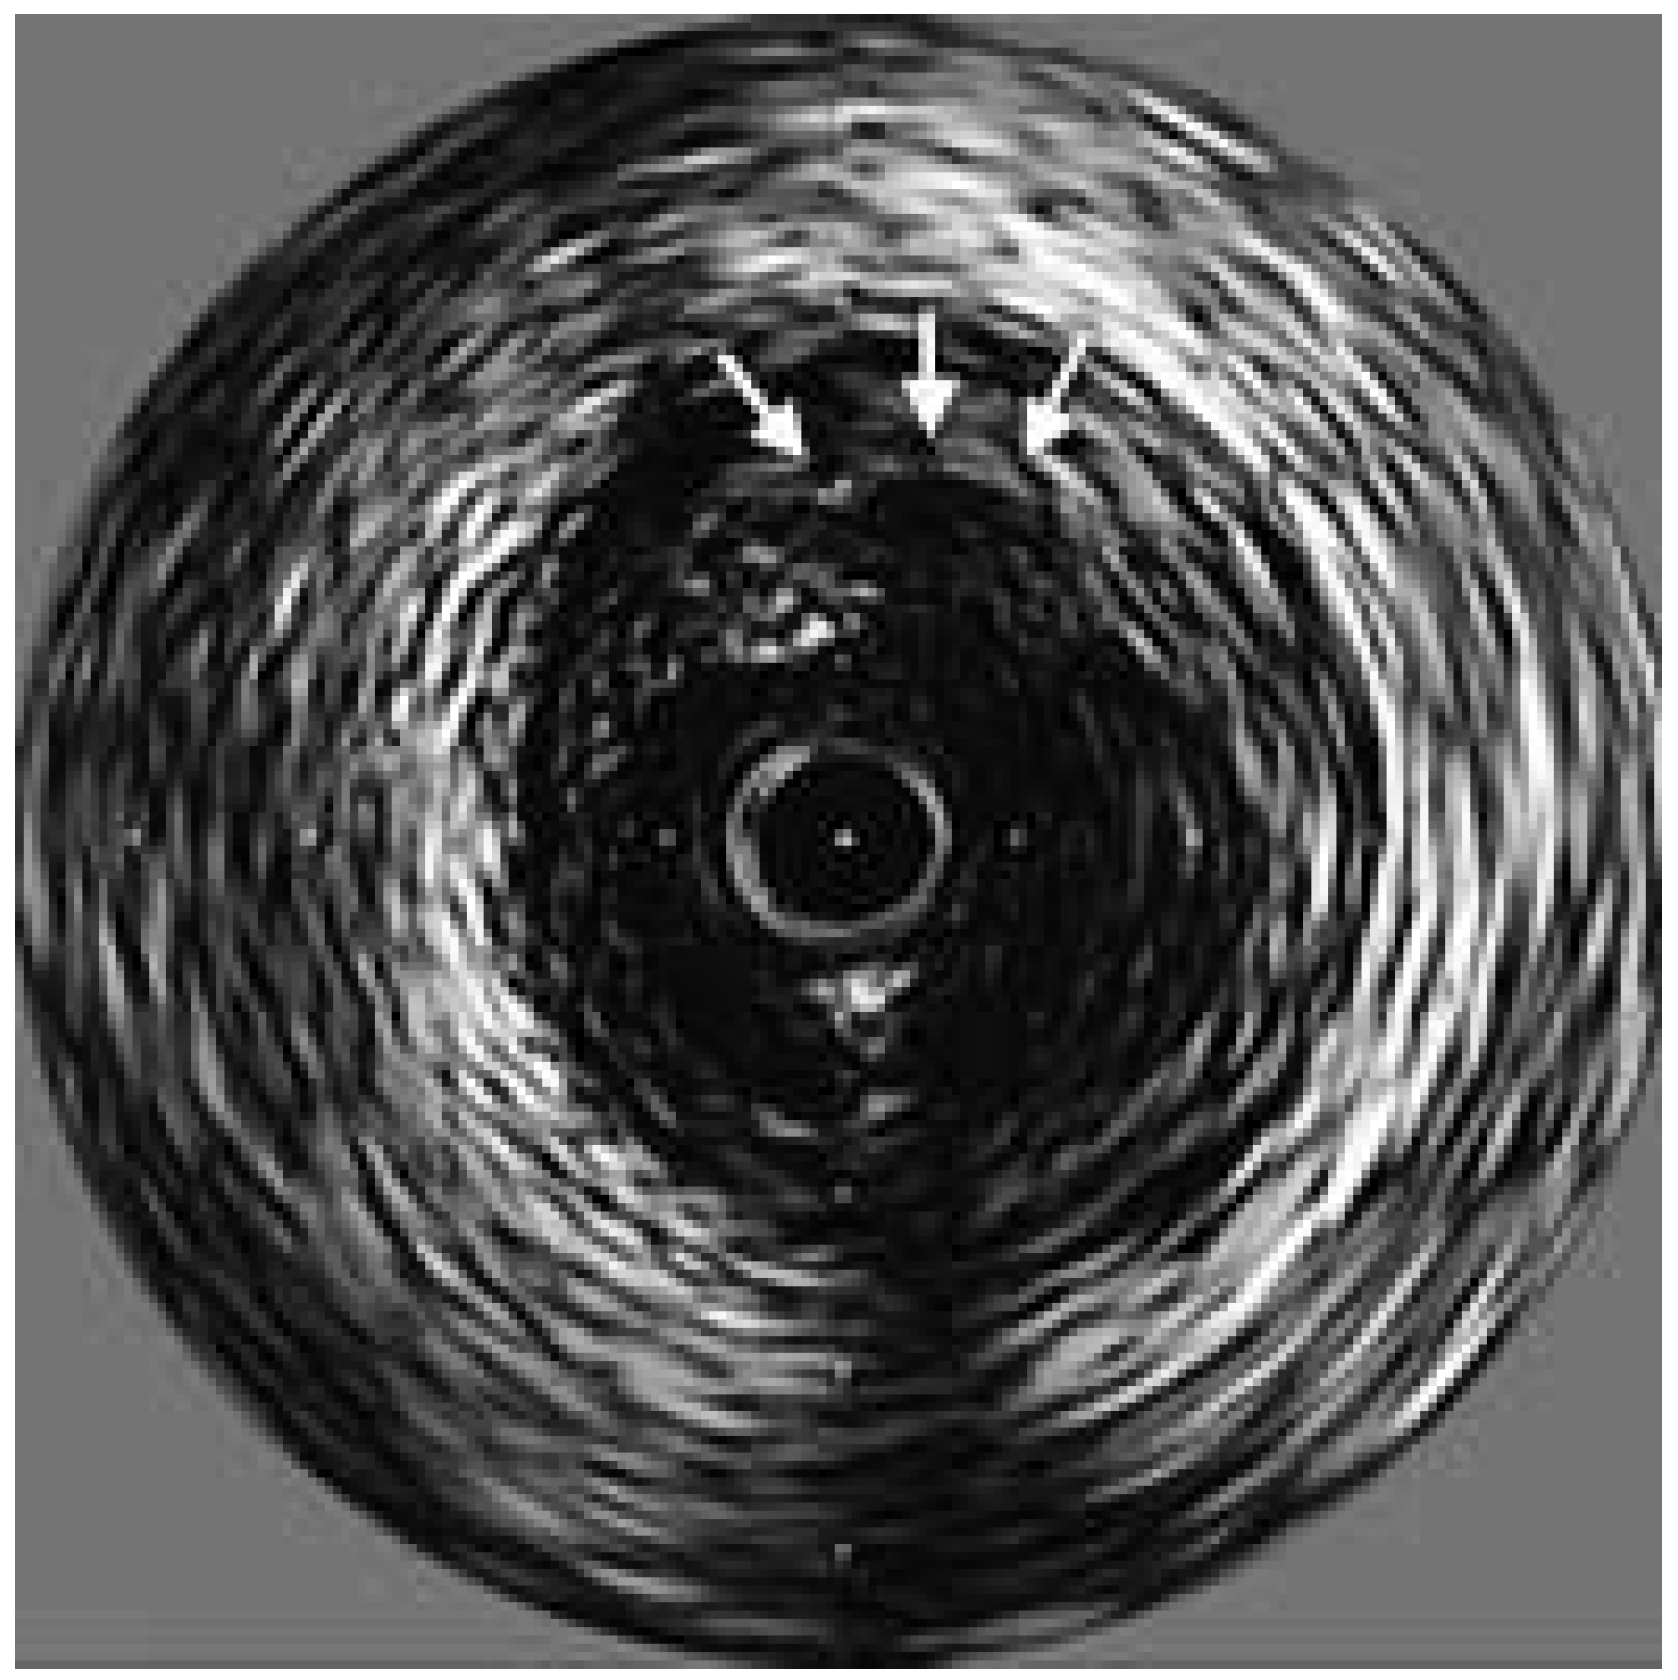

Intra-vascular ultrasound